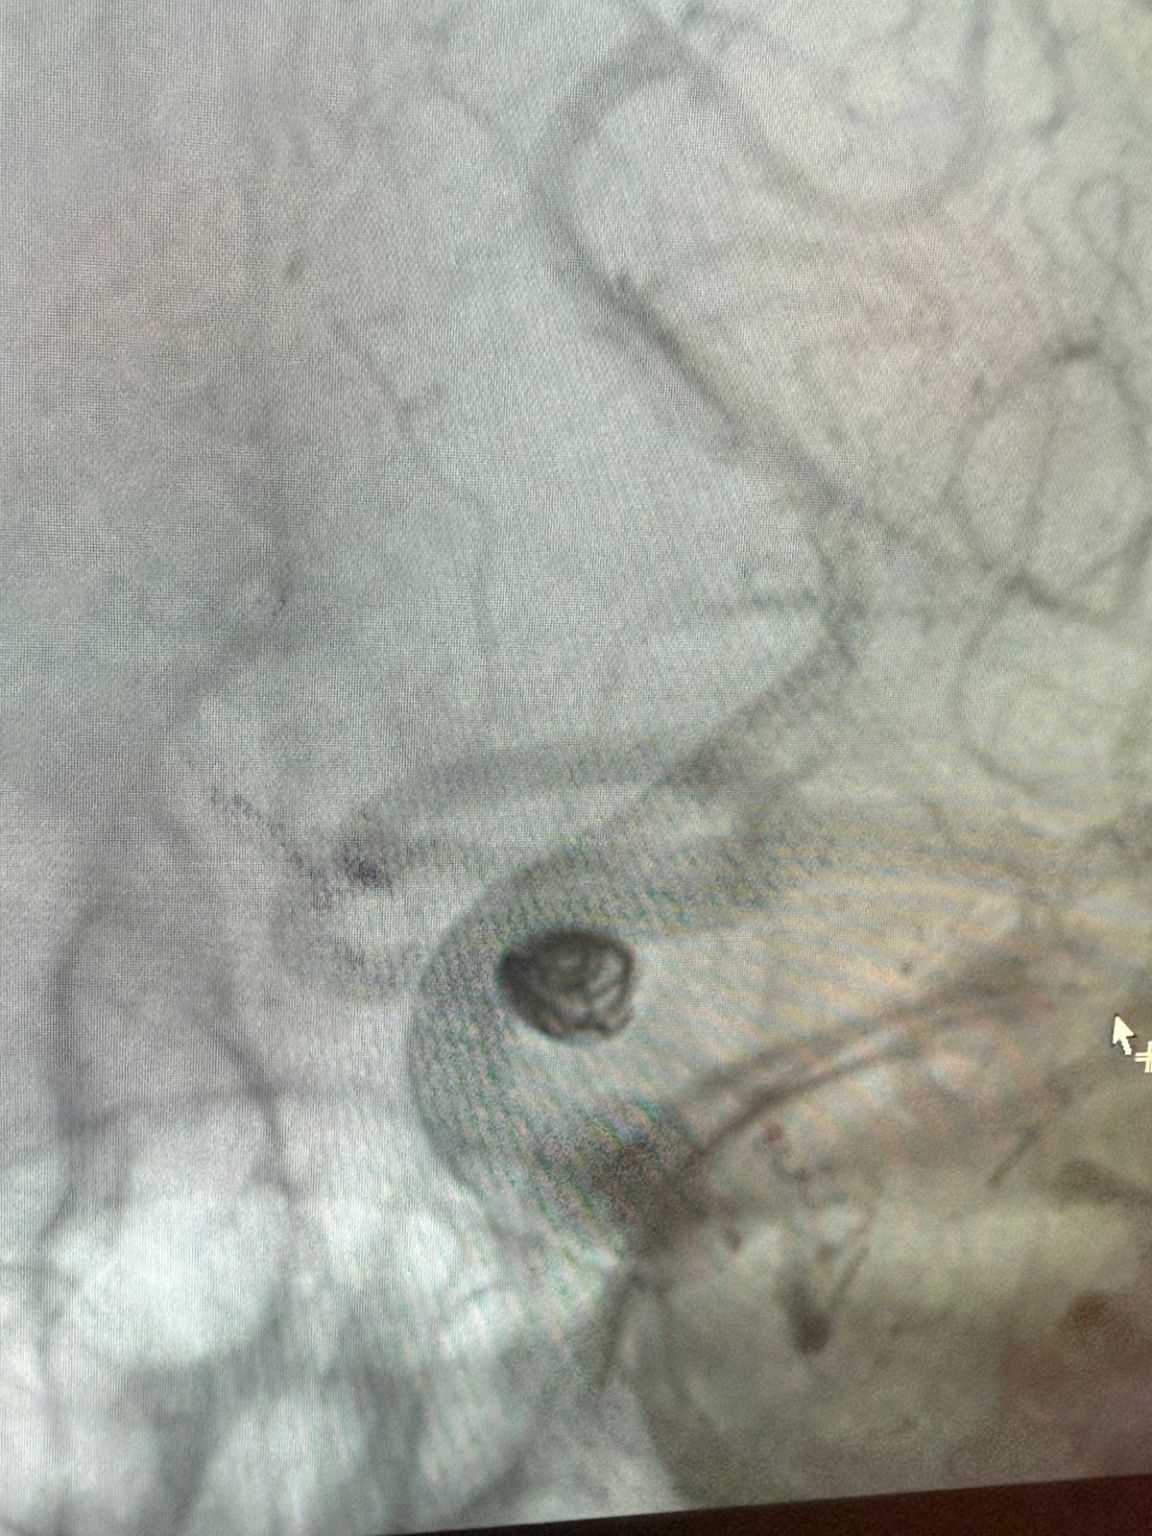

Siamo lieti di condividere una recente procedura di successo presso Clínica Alma Mater, Medellín, eseguita dal Dr. Jorge Mutis.

Il trattamento ha utilizzato la Nuva®Deviatore di flusso (TJED-D 5.0-14), Perdenser®Bobina 3D e Fepass®Microcatetere (TJMC18 Plus) per un aneurisma dell'arteria comunicante posteriore.

Il dottor Mutis ha evidenziato l'eccellente visibilità del dispositivo e ha notato che il recupero è stato regolare. Ha espresso grande soddisfazione per l'esito finale.